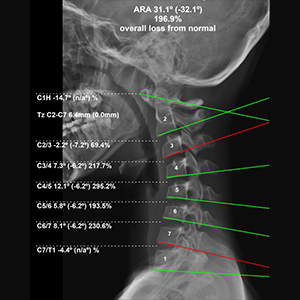

The Elevation Health Approach: Objective Data, Measurable Outcomes When it comes to spine and injury care—especially for patients who have been injured in a car accident—one of the biggest frustrations is uncertainty. Patients are often told they should feel better, that healing “takes time,” or that pain levels are subjective. At Elevation Health, the approach […]